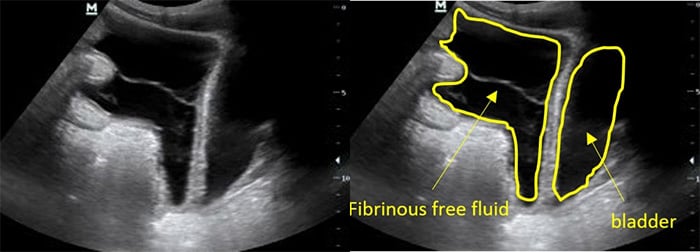

- Ascites (Fig. 6)

- Ascites is a common finding in many disease entities however in the patient with HIV from a TB endemic area, it is highly suggestive of TB.

- With or without fibrinous debris: OR 2.221

- Without fibrinous stranding: PPV= 73% NPV = 33%18

- With fibrinous stranding: PPV = 86% NPV= 41%18

Figure 7. Fibrinous ascites in pelvis sagittal view

Figure 8. RUQ free fluid with fibrinous stranding and hyperechoic liver lesions

- Free abdominal fluid will have irregular sharp edges as the fluid surrounds loops of bowel, while fluid contained in the bladder should have smooth rounded edges (Figure 7).